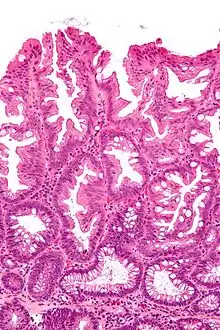

Tubulovillous adenoma (tubular component – left of image, villous component – right of image). H&E stain.

Tubulovillous adenoma

Tubulovillous adenoma, TVA are considered to have a higher risk of becoming malignant (cancerous) than tubular adenomas.[9]